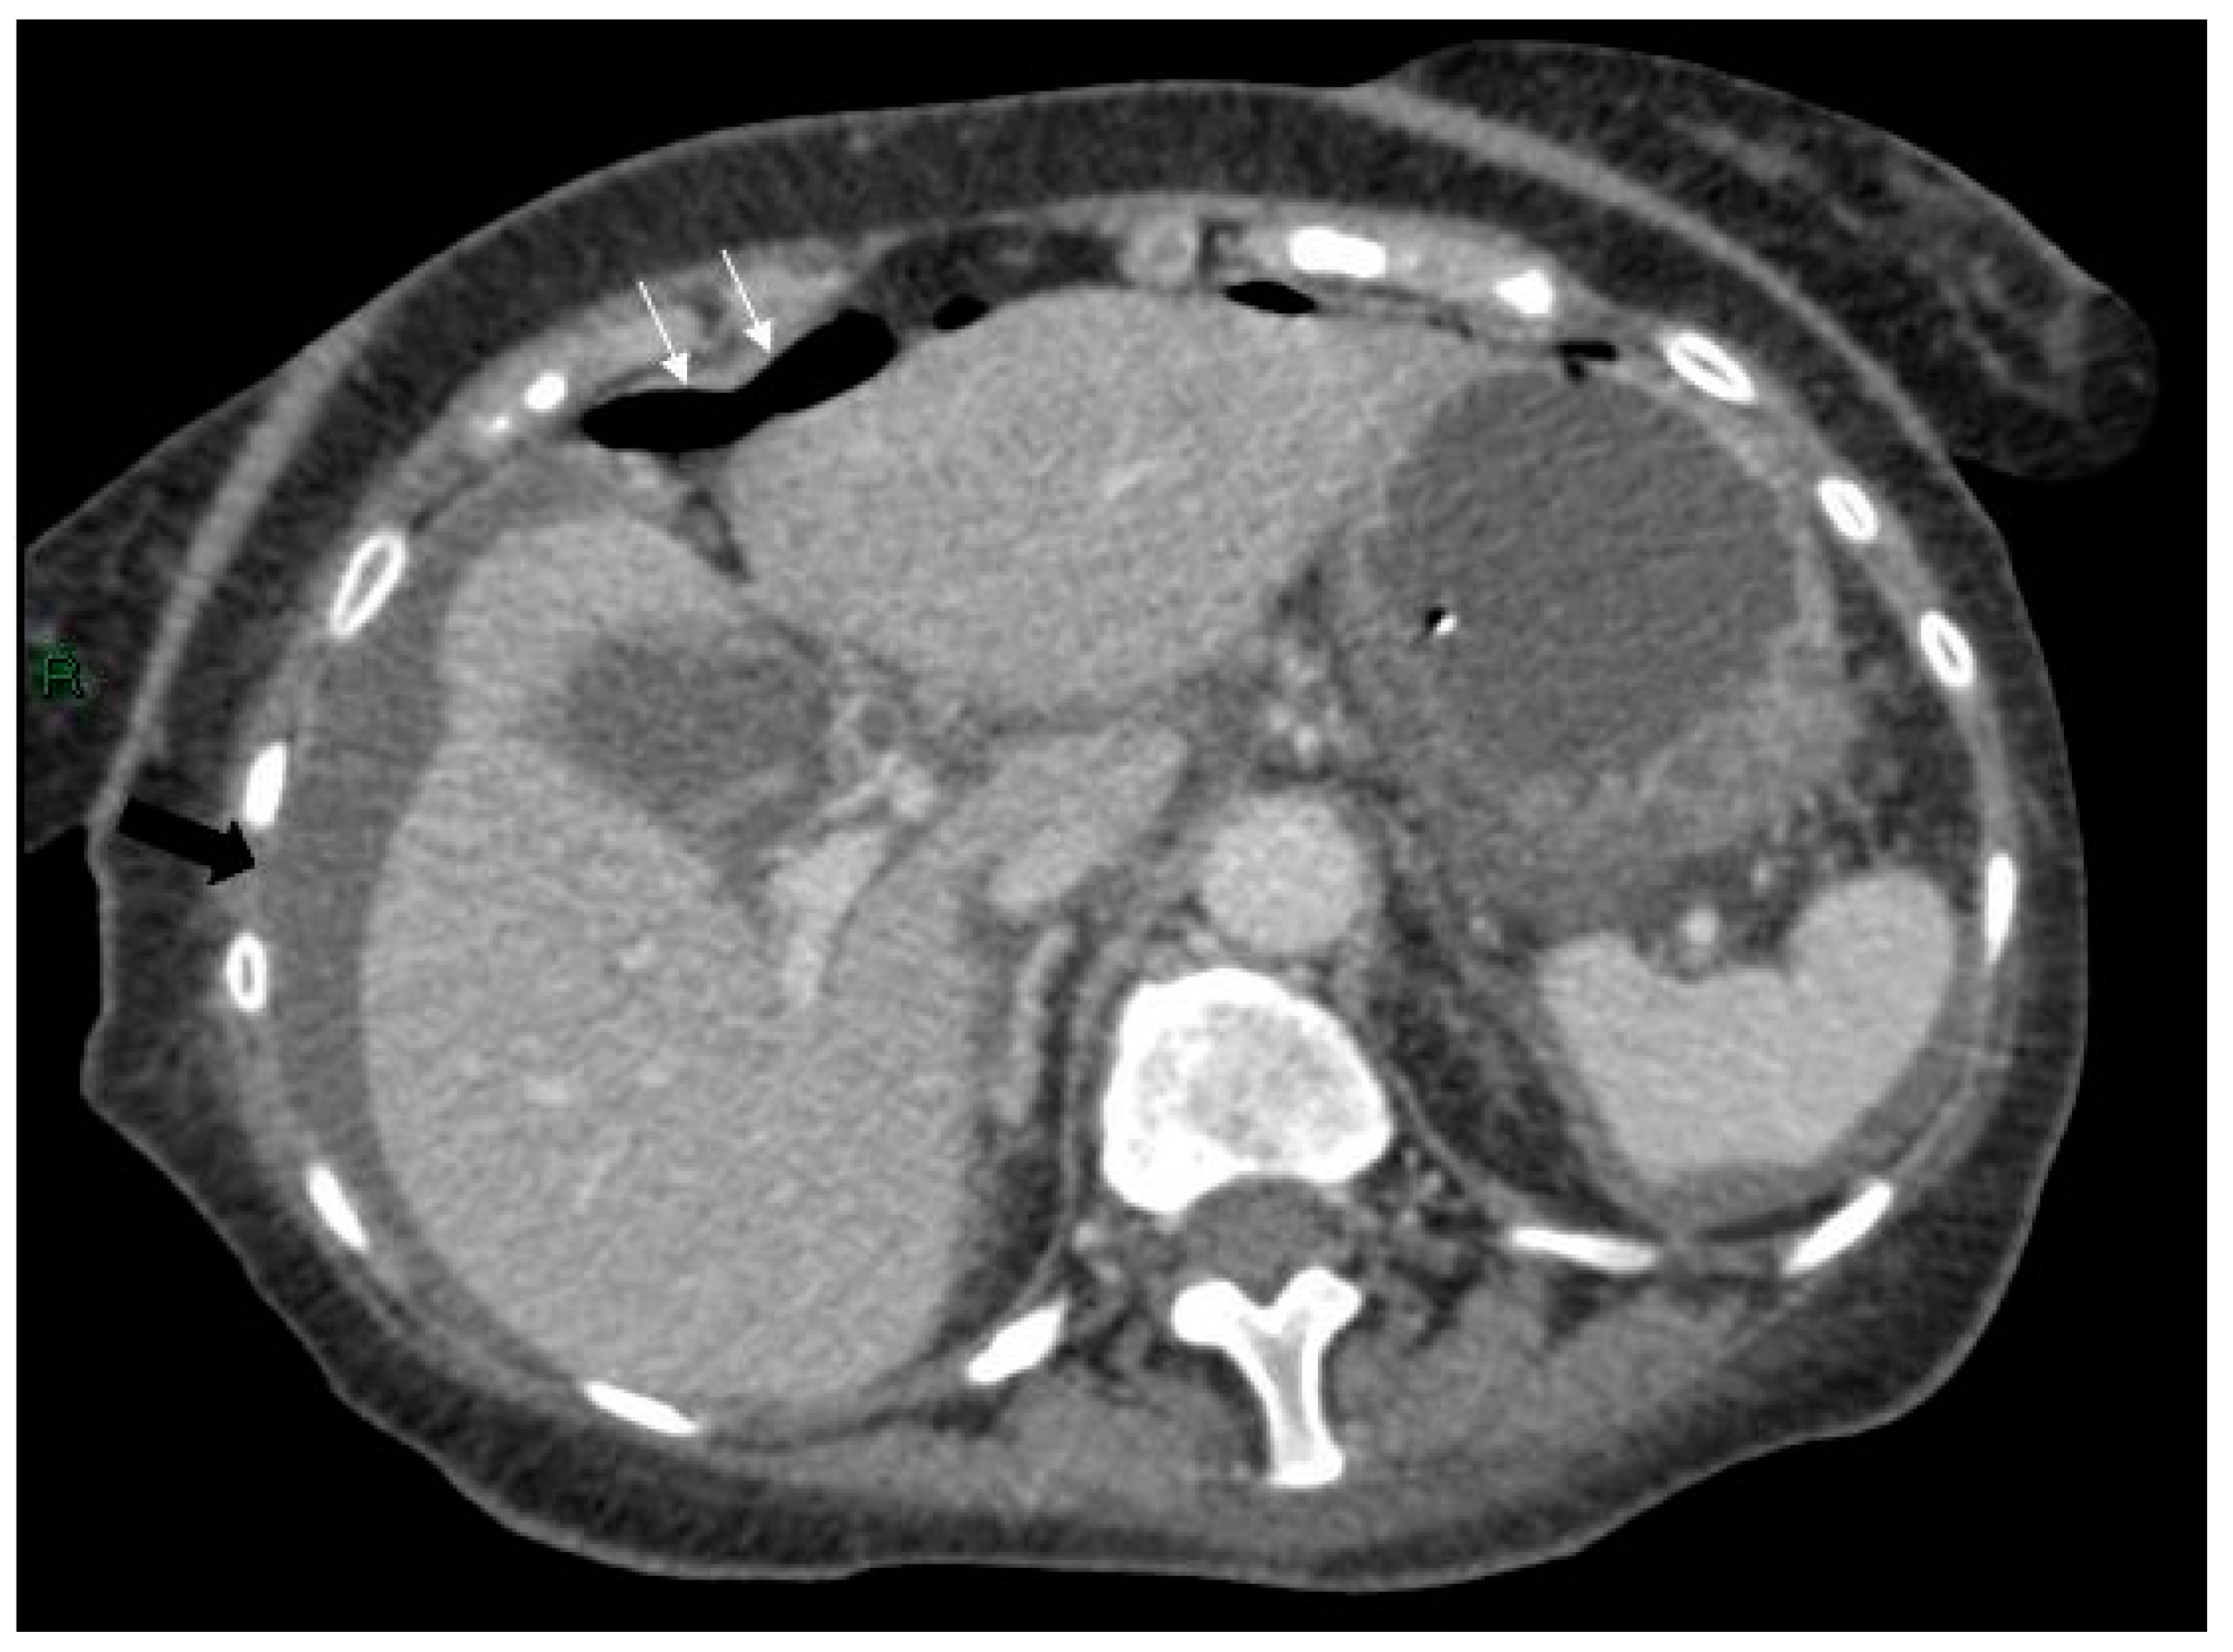

On day six her clinical condition deteriorated, she was pyrexial and haemodynamically unstable. The patient complained of increased abdominal pain and had a raised white cell count and a raised arterial lactate level. An erect chest x-ray revealed free air under the right hemidiaphragm. Following initial resuscitation and administration of antibiotics, a CT was performed revealing the known pseudocyst with anterior compression of the stomach, free fluid in the abdomen and considerable free intra-abdominal air (Figure 3, Figure 4 and Figure 5).

Figure 3.

Axial CT scan of the abdomen showing free air anterior to the liver (white arrows) and free fluid around the liver and spleen (black arrows).

Figure 4.

Axial CT scan of abdomen showing free air anterior to the liver (white arrows) and free fluid around the liver and spleen (black arrows).